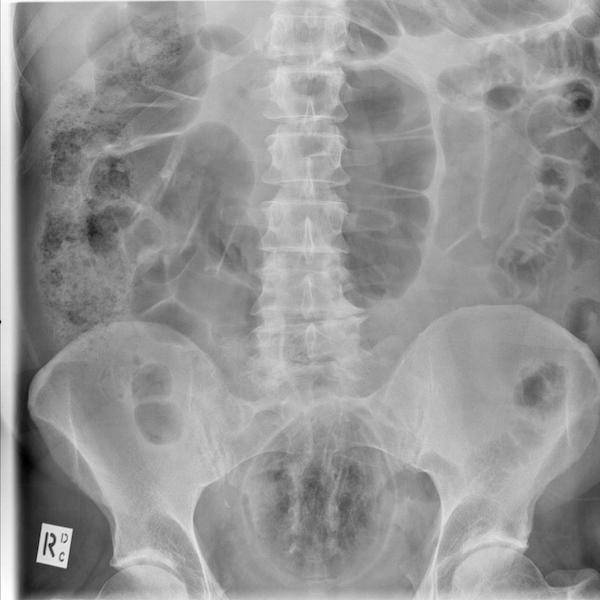

78 different pieces of cutlery in a woman’s stomach.